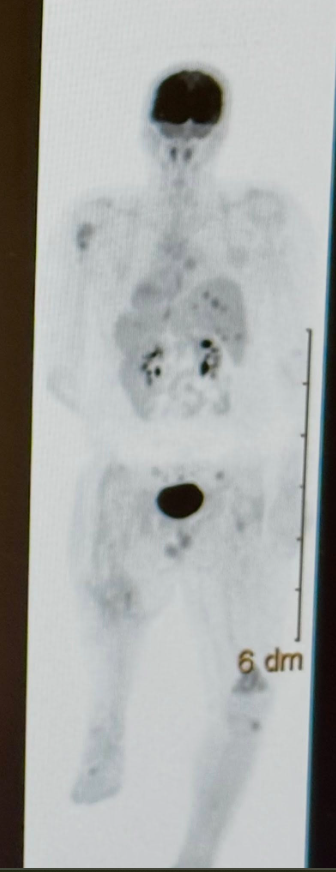

Will’s journey has entered a quiet, painful chapter — one marked not by headlines or urgency, but by heavy reflection and difficult truths.

Recent setbacks have forced doctors and loved ones to reassess the road ahead. Every option now carries weight. Every conversation matters. This is no longer about quick decisions or easy answers — it’s about endurance. 💔🛡️

In moments like this, the limits of medicine become clearer, and the depth of love becomes unmistakable. Will continues to show remarkable courage, facing each hour with a steadiness that humbles everyone around him. His family remains beside him, navigating the unknown with faith, grace, and unwavering devotion. 🕯️✨